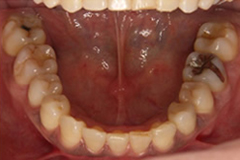

治療後はきれいに整っています。

左上下顎臼歯部に著しい叢生があり、下顎臼歯部が大きく舌側へ傾斜していました。左はもちろん、右側も歯並びが崩れていて、右ではほとんど咬んでいなかったそうです。